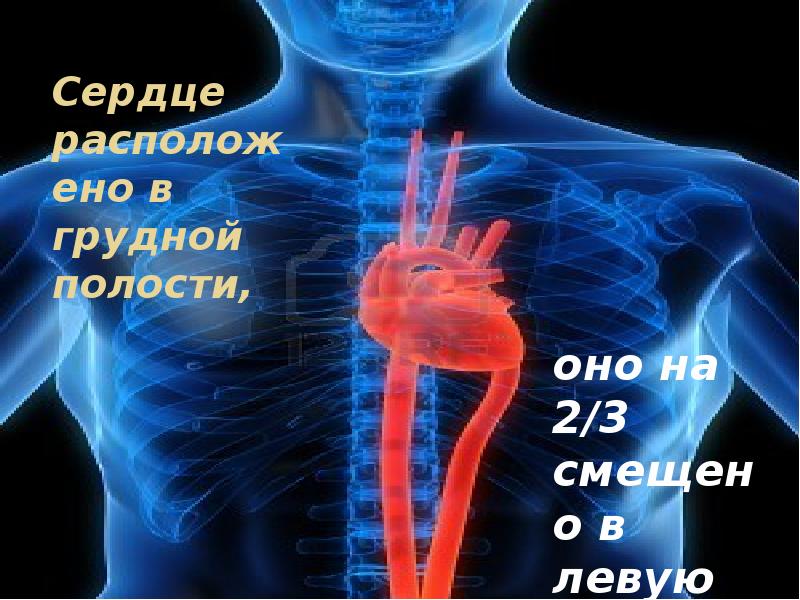

Где находится сердце у человека.

Сердце у человека располагается.

Сердце у человека располагается в грудной полости.

Расположение сердца у человека.

Анатомическое расположение сердца.

Сердце в грудной клетке расположено.

Где расположено сердце у человека анатомия.